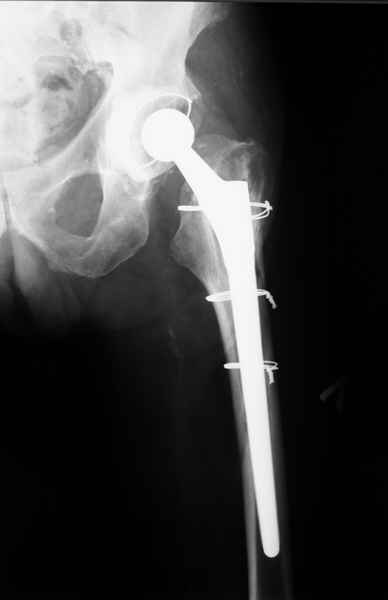

Уважаемые коллеги, продолжая дискуссию, начатую на "Вреденовских чтениях", хочу сказать, что принципиально сущестует два возможных варианта лечения.

1.Остеосинтез на ножке. Мне кажется, что применительно к этому случаю малоперспективный вариант. Синтез хорош, когда можно его выполнить в малоинвазивном исполнении и достигнуть стабильности. Действительно, если ножка б/цементной фиксации после этого не будет иметь фиксации, то ревизия не будет иметь проблем. В представленном случае стабильность синтеза сомнительная, а проведение доп.иммобилизации приведет к контрактуре суставов.

2. Применение ножки дистальной фиксации, мы отдаем предпочтение ножке Вагнера с фиксацией проксимального отдела на ножке. Более травматичное вмешательство, но при стабильной фиксации ножки реабилитация идет в обычном режиме.

Хочется показать два подобных случая, П-ка З. 72 лет и п-т Г. 80 лет. Сразу принимаю замечание, что это были ножки цементной фиксации, просто под руками не было бесцементника.

С уважением, Р.Тихилов

Произведено закрытое удлинение ножки эндопротеза с помощью ретроградного интрамедуллярного стержня. Продолжительность операции 3 часа. Два из них закрытое восстановление длины бедра диистрактором

таз-бедро.